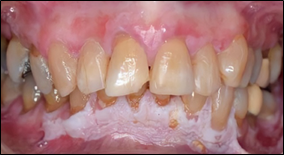

Erythroplakia

Predominantly bright red velvety plaque lesion of oral mucosa that cannot be characterized clinically or histologically as any other definable lesion.15,18 Erythroplakia most frequently occur in male aged 50-70. Common site of involvement is tongue, buccal mucosa, floor of mouth, retromolar pad, and soft palate. In some people the lesion is associated with burning sensation17,19 (Figure 2).